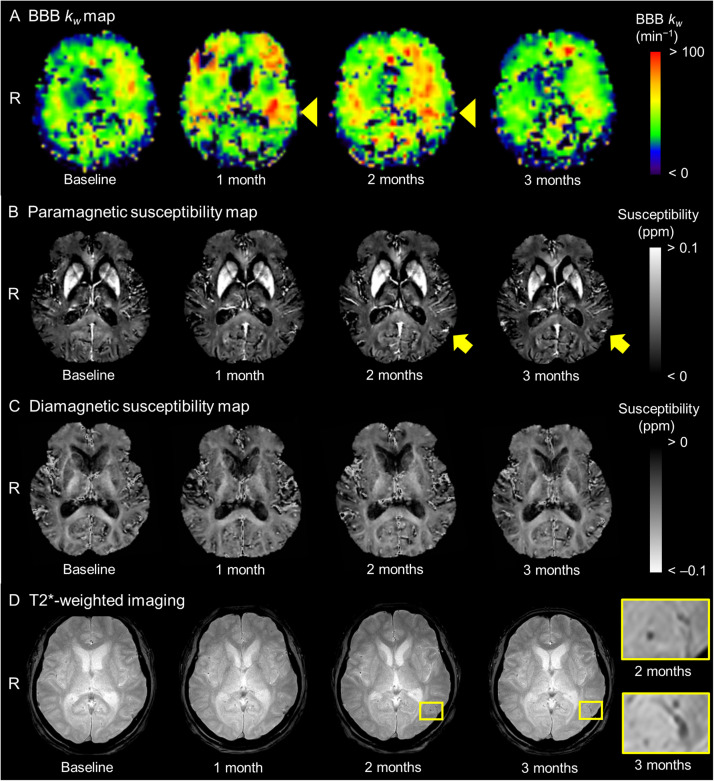

Blood-brain barrier water exchange and paramagnetic susceptibility alterations during anti-amyloid therapy: preliminary MRI findings.

抗淀粉样蛋白治疗期间血脑屏障水交换和顺磁敏感性改变:初步MRI结果。